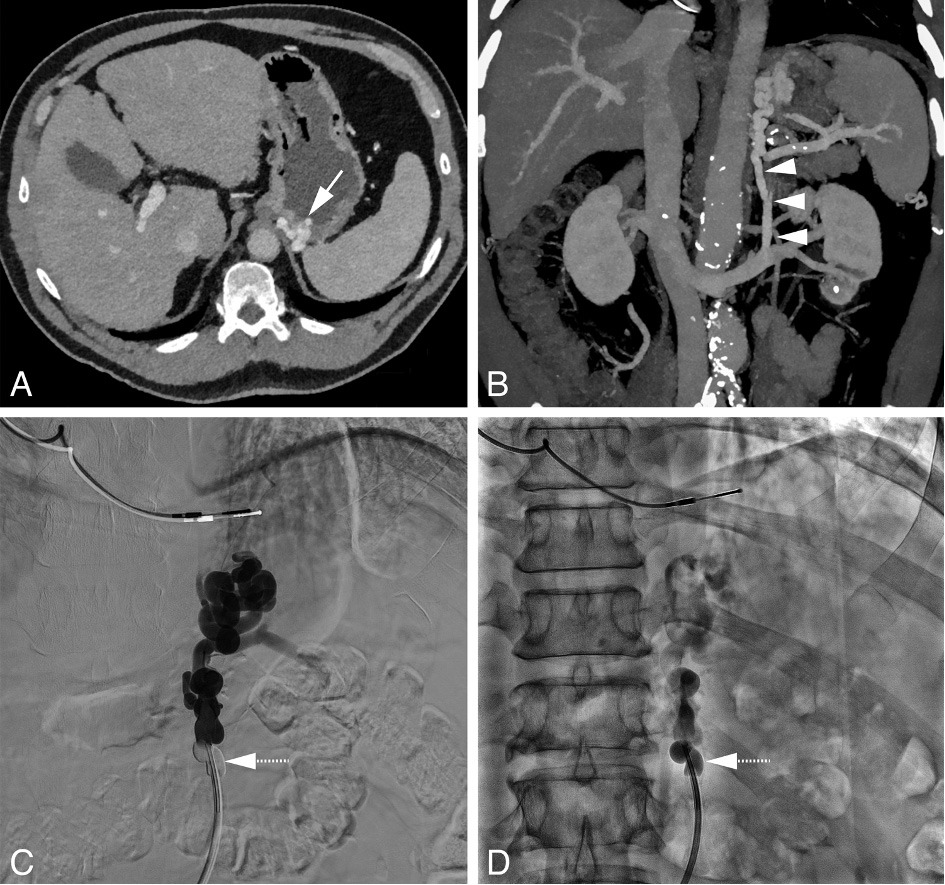

Figure 2: BRTO in a 64 year-old-male with a history of alcohol-induced liver cirrhosis who presented at the emergency department with melena. A) Axial CT image showing morphological changes of the liver consistent with cirrhosis and a gastric varix (white arrow). B) Coronal maximum intensity projection (MIP) demonstrating a splenorenal shunt (arrowheads). C) Venography with an occlusion balloon (doted arrow; also in D) in place with opacification of the splenorenal shunt and gastric varices. D) Fluoroscopy image after injection of a mixture of polidocanol 3% : contrast medium : air (1:1:2) with contrast staining of the splenorenal shunt and gastric varices.

Suitable candidates for BRTO are patients with a splenorenal shunt. Using a transfemoral approach, a catheter and guidewire are advanced via the left renal vein. The portosystemic shunt is then catheterized and occluded using an occlusion balloon (see figure 1). The purpose of the occlusion balloon is to block the flow of blood from the portal to the systemic circulation and allow retrograde filling of gastric varices with a sclerosing agent. A venogram is performed to ensure successful occlusion of the portosystemic shunt and filling of the gastric varices. It is not uncommon to see contrast agent flowing to the systemic circulation through branches originating from the portosystemic shunt, most commonly the left inferior phrenic vein. These side branches are then first embolized with coils to prevent leakage of the sclerosing agent to the systemic circulation. After successful occlusion of the shunt, a sclerosing agent, such as polidocanol or sodium tetradecyl sulfate, is injected directly into the gastric varices through the end-hole of the occlusion balloon or a micro-catheter.